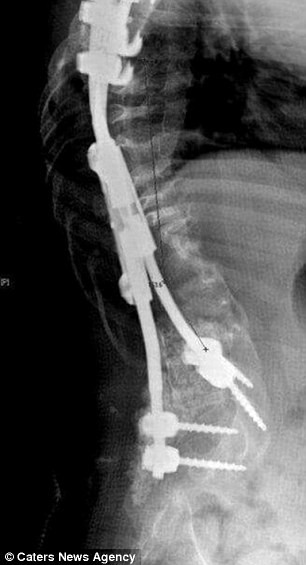

Kể từ đó Ellisha phải phẫu thuật thêm nhiều lần, trong đó có phẫu thuật làm giảm tốc độ gãy gập, phẫu thuật đưa thanh titan vào để ép thẳng xương sống rồi lại kéo dài những thanh nẹp này theo sự phát triển chiều cao của bé.

Ellisha hiện mang trong người 2 thanh titan, 8 đinh vít và 4 cái nẹp để cố định xương sống. Cô bé đang chuẩn bị phẫu thuật lần thứ 13 để tiếp tục kéo dài thanh kim loại.